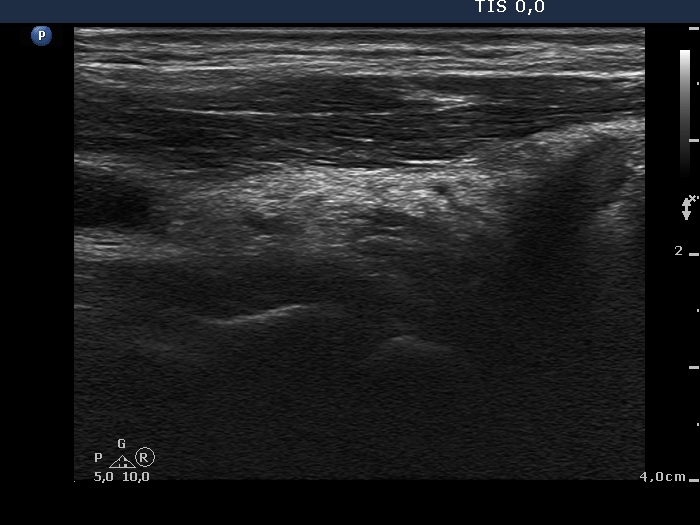

Eleven months after surgery (fourth row of images)

Clinical data. The patient underwent on ablative radioiodine therapy and was well.

Palpation: no abnormality.

Functional state: subclinical hyperthyroidism on daily 175 microgram levothyroxine (TSH 0.06 mIU/L, FT4 22.1 pM/L, thyroglobulin < 0.1 ng/mL, anti-hTg 2 U/mL).

Ultrasonography: There was no thyroid parenchyma in thyroid beds. The regenerative mass disappeared.